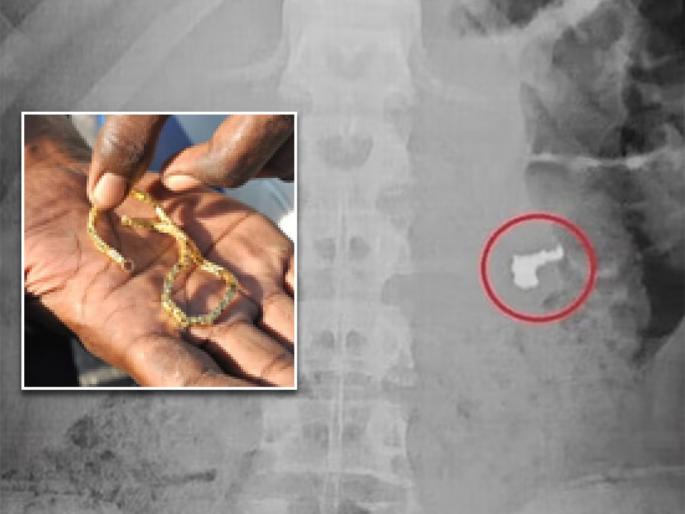

पण चोरांकडे काहीच सापडलं नाही आणि उलट चोर म्हणाले की, तुमच्याकडे काय पुरावा आहे की, आम्ही सोन्याची चेन चोरी केली. काही न मिळाल्यानंतर संशयितांना टेस्ट करण्यासाठी नेण्यात आलं. त्यांचा एक्स-रे केला तर सगळे हैराण झाले.

एका चोराच्या एक्स-रेमध्ये स्पष्ट दिसत होतं की, त्याच्या पोटात सोन्याची चेन आहे. त्यांना हॉस्पिटलमध्ये नेण्यात आलं आणि त्याच्यावर उपचार सुरू आहेत.